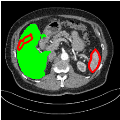

Our primary findings comparing the proposed model to baseline fully-supervised models when segmenting the liver from the LiTS dataset are reported in Table 1. The reported results demonstrate that our SAM-Mix model consistently achieves higher Dice scores compared to the fully supervised baselines as well as the two-stage SAM-PP method. Against U-Net, the best-performing fully supervised method, the SAM-Mix variant trained on 50 segmentation labeled slices (SAM-Mix-50), achieves a Dice score improvement of 5.9%. In terms of Hausdorff distance, while the fully-supervised baselines do slightly outperform SAM-Mix-5 and SAM-Mix-100, SAM-Mix-50 does achieve a lower Hausdorff distance by 22.38%. Qualitative evaluation as shown in Figs. 3 further affirms the superiority of SAM-Mix over baseline and existing fully-supervised methods as well as the two-stage SAM-PP variants. Furthermore, the boxplot visualization in Fig. 2 showcases consistently improved performance by SAM-Mix outperforming all the fully supervised and semi-supervised methods.

![]() |

| U-Net | nnU-Net | TransU-Net | SAM-PP-0 | SAM-PP-5 |

| SAM-PP-50 | SAM-PP-100 | SAM-Mix-5 | SAM-Mix-50 | SAM-Mix-100 |